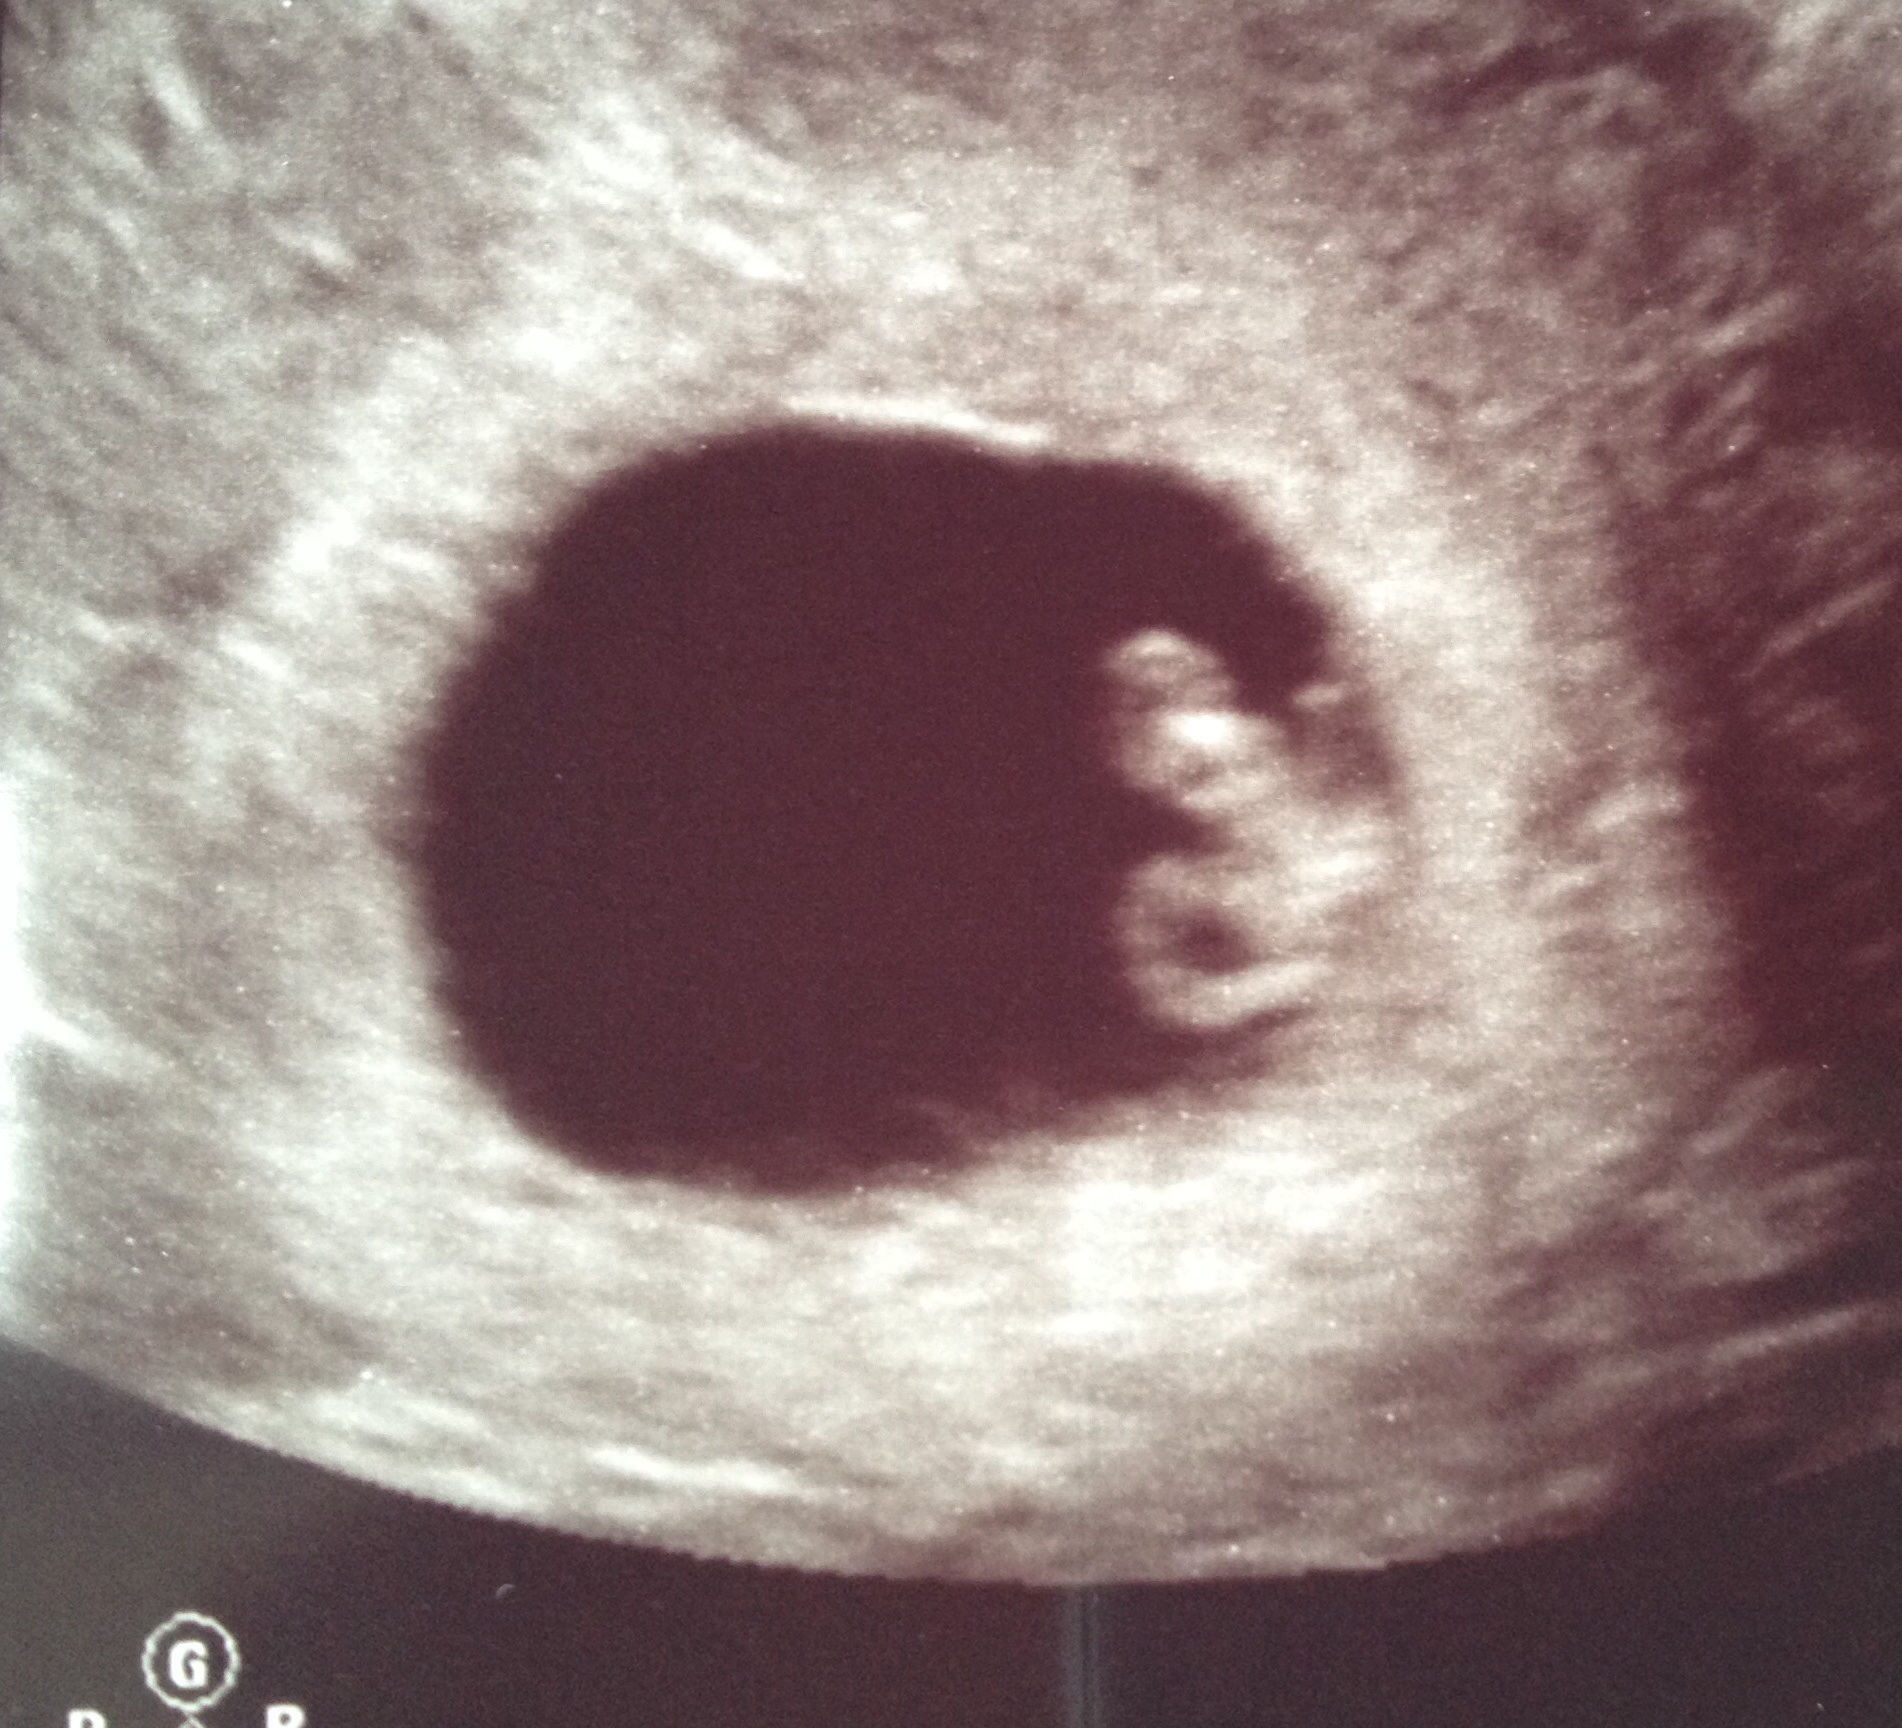

• Mine is an IVF pregnancy, so they monitor closely early on. First ultrasound was at 6w5d; we saw the yolk sac and fetal pole with a heartbeat of 127 bpm. It was such a relief to hear that everything was measuring on track! 2nd ultrasound was yesterday at 8w1d and I was measuring 1 day ahead. It's really starting to look like a baby now, with a head, body, and nubby arms and legs; it was incredible to see! Heartbeat was at 168 bpm, and we saw where the brain is developing, even got to see the umbilical cord. One more ultrasound with my RE at 10w5d before he releases me to the OB.